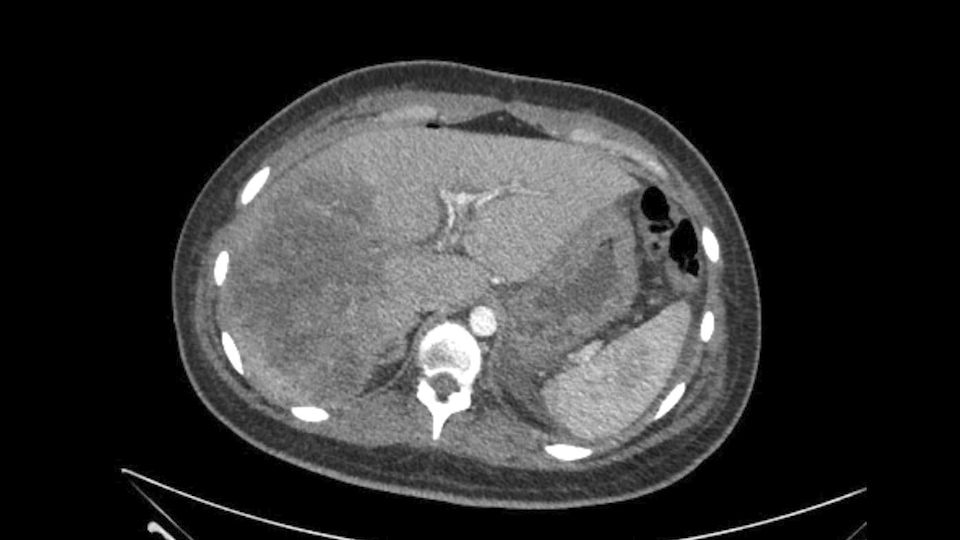

On post-operative Day 1, the patient required monitoring in the intensive care unit due to decrease in consciousness. The patient's CT scan revealed portal vein thrombosis, right liver ischemia and ascites. With deterioration of consciousness and Grade 2 encephalopathy, on post-operative Day 4 she was transferred to an HPB centre.

Imaging revealed a right liver infarction, right poral vein thrombosis extending to the main portal vein. Both the right and left hepatic arteries were absent but normal arterial flow was identified through an accessory branch off the left gastric artery. The consensus diagnosis is a vasculobiliary injury.